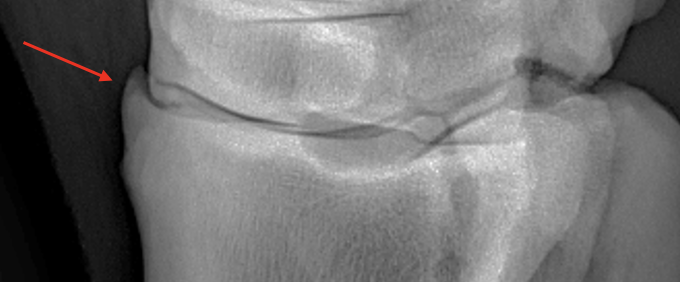

What is shown in these images?

Left: osteochondrosis of lateral trochlear ridge of talus

-“missing” bone that is cartilaginous instead of mineralized

Right: osteochondrosis of lateral trochlear ridge of talus

-lesion is the divot seen on lateral trochlear ridge

-red arrow is pointing to normal variation of the medial trochlear ridge